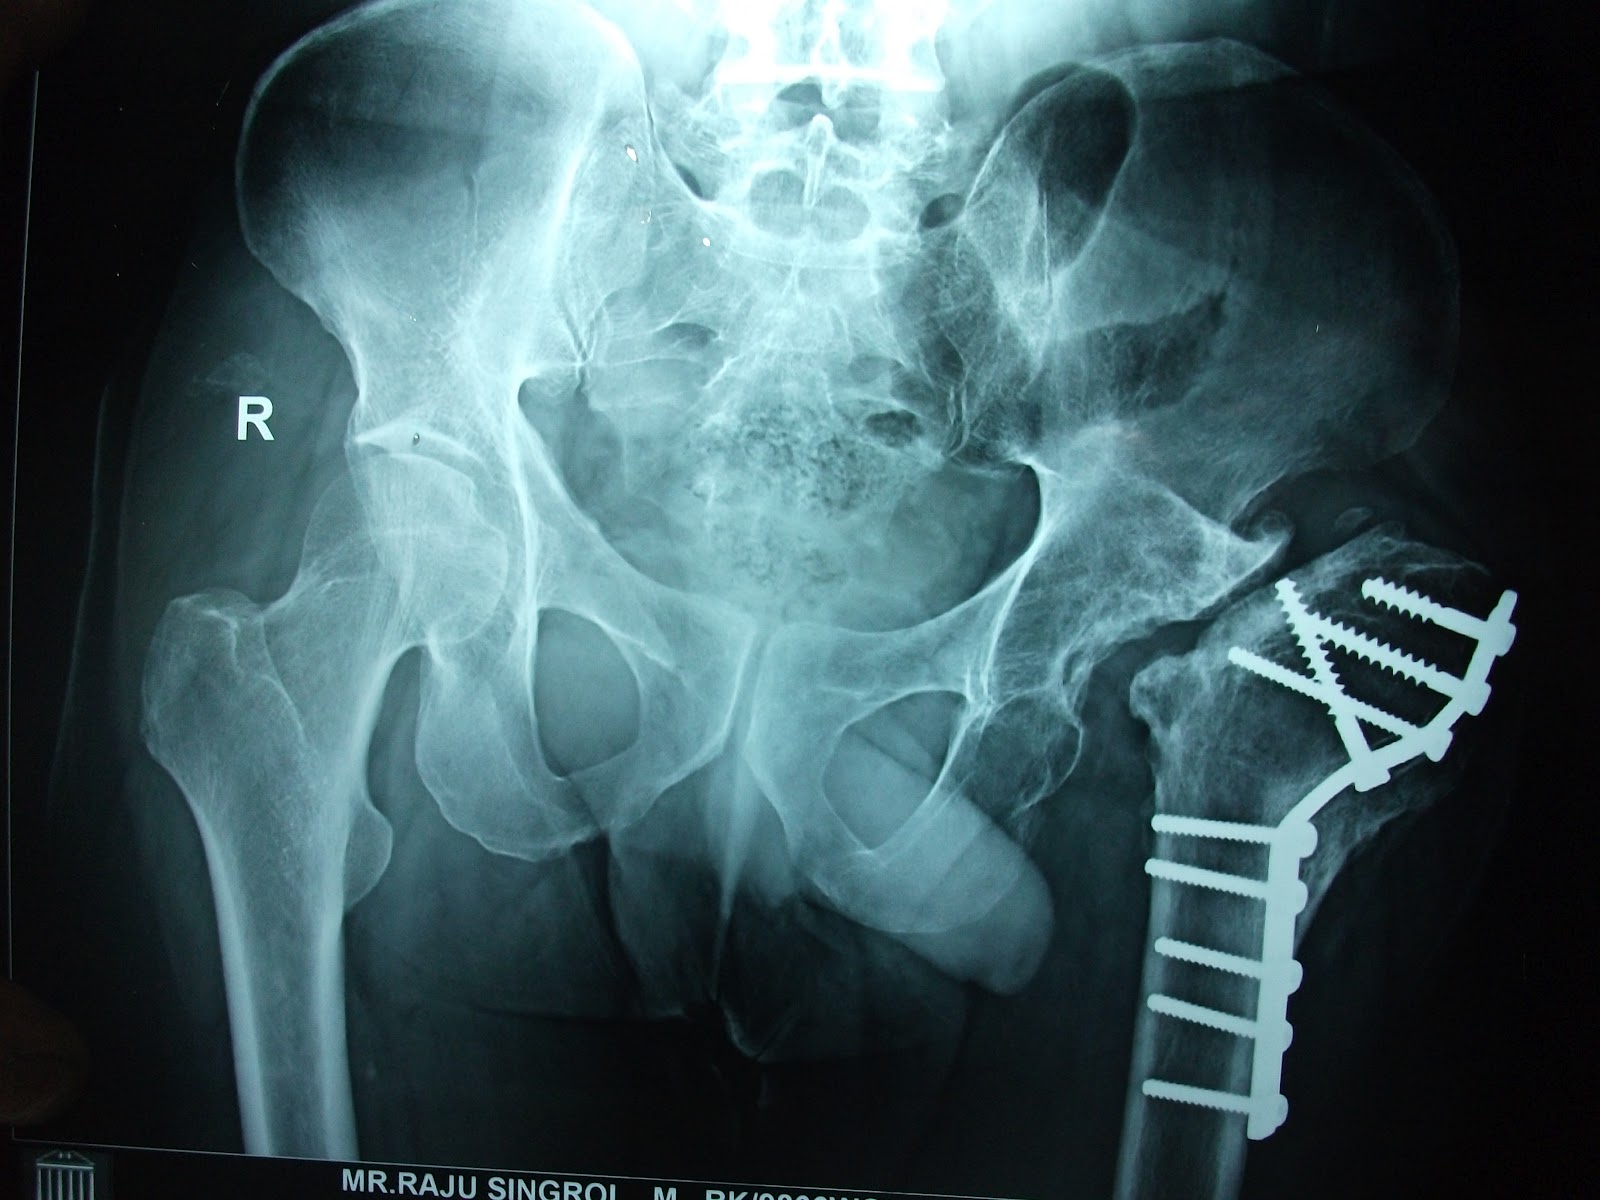

Medical Apparatus Imaging Guide fracture fixation Girdlestone X Ray girdlestone arthroplasty and hip arthrodesis using the ilizarov external fixator as a salvage method in the management. Radiopaque material in the left femoral intramedullary. The girdlestone resection arthroplasty (gra) is a salvage procedure for a recurrent or persistent. girdlestone is one of the options for treating an infected hip arthroplasty (along with isolated. the girdlestone procedure (also. Girdlestone X Ray.

Right hip xray after the insertion of the second antibiotic cement Girdlestone X Ray the girdlestone procedure (also known as a femoral head ostectomy or girdlestone resection arthroplasty) is an. girdlestone arthroplasty and hip arthrodesis using the ilizarov external fixator as a salvage method in the management. Radiopaque material in the left femoral intramedullary. girdlestone is one of the options for treating an infected hip arthroplasty (along with isolated. The girdlestone. Girdlestone X Ray.